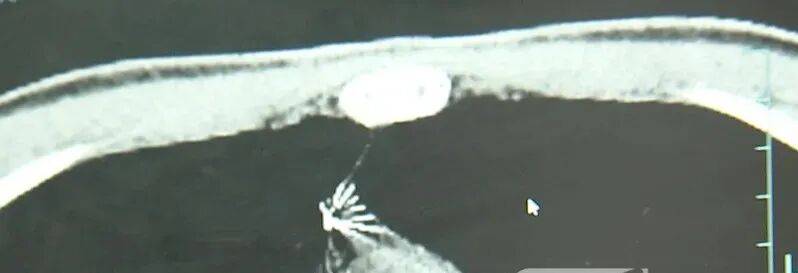

近日,安徽17岁小伙小陆参加征兵体检,胸片结果显示:胸腔内有一处金属高密度影,形态细长,像一根针币圈社区介绍

进一步的CT检查确认,异物是一枚金属针,斜插在肺组织内,位置十分凶险币圈社区介绍

杭州市第一人民医院心胸外科副主任冯兴说:“我们看到这个针的尖锐部,正好指向他体内的一个大血管,边上是上腔静脉和胸主动脉,因此这个针稍有不慎,就有可能造成周边血管的损伤,甚至危及生命币圈社区介绍。”

医生推测,那枚针很可能就是在那时候扎入体内的币圈社区介绍。针在小陆体内滞留了十几年,既没有引发感染,也没有造成气胸,堪称医学奇迹。上周四,医院为小陆实施了mini单孔胸腔镜微创手术,切口仅两厘米左右,成功将针完整取出。